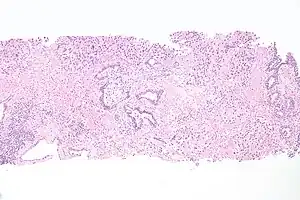

_pT1.JPG.webp) | |

| Histopathology of transitional carcinoma of the urinary bladder. Transurethral biopsy. Hematoxylin and eosin stain. | |

_at_trigone.jpg.webp) Histopathology of urothelial carcinoma of the urinary bladder, showing a nested pattern of invasion. Transurethral biopsy. Hematoxylin and eosin.

Histopathology of urothelial carcinoma of the urinary bladder, showing a nested pattern of invasion. Transurethral biopsy. Hematoxylin and eosin._at_trigone.jpg.webp) Histopathology of urothelial carcinoma of the urinary bladder.

Histopathology of urothelial carcinoma of the urinary bladder._at_trigone.jpg.webp) Histopathology of urothelial carcinoma of the urinary bladder.

Histopathology of urothelial carcinoma of the urinary bladder. Micrograph of urethral urothelial cell carcinoma. Hematoxylin and eosin stain.

Micrograph of urethral urothelial cell carcinoma. Hematoxylin and eosin stain.